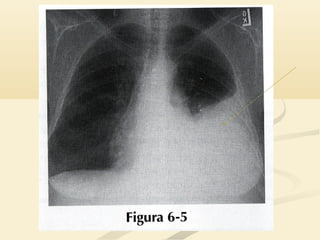

 La consolidación del LSI borrará la aurícula izquierda,La consolidación del LSI borrará la aurícula izquierda,

el botón aórtico y el mediastino anterior y medioel botón aórtico y el mediastino anterior y medio..

 La consolidacióndel LSI borrará la aurícula izquierda,La consolidación del LSI borrará la aurícula izquierda, el botón aórtico y el mediastino anterior y medioel botón aórtico y el mediastino anterior y medio..